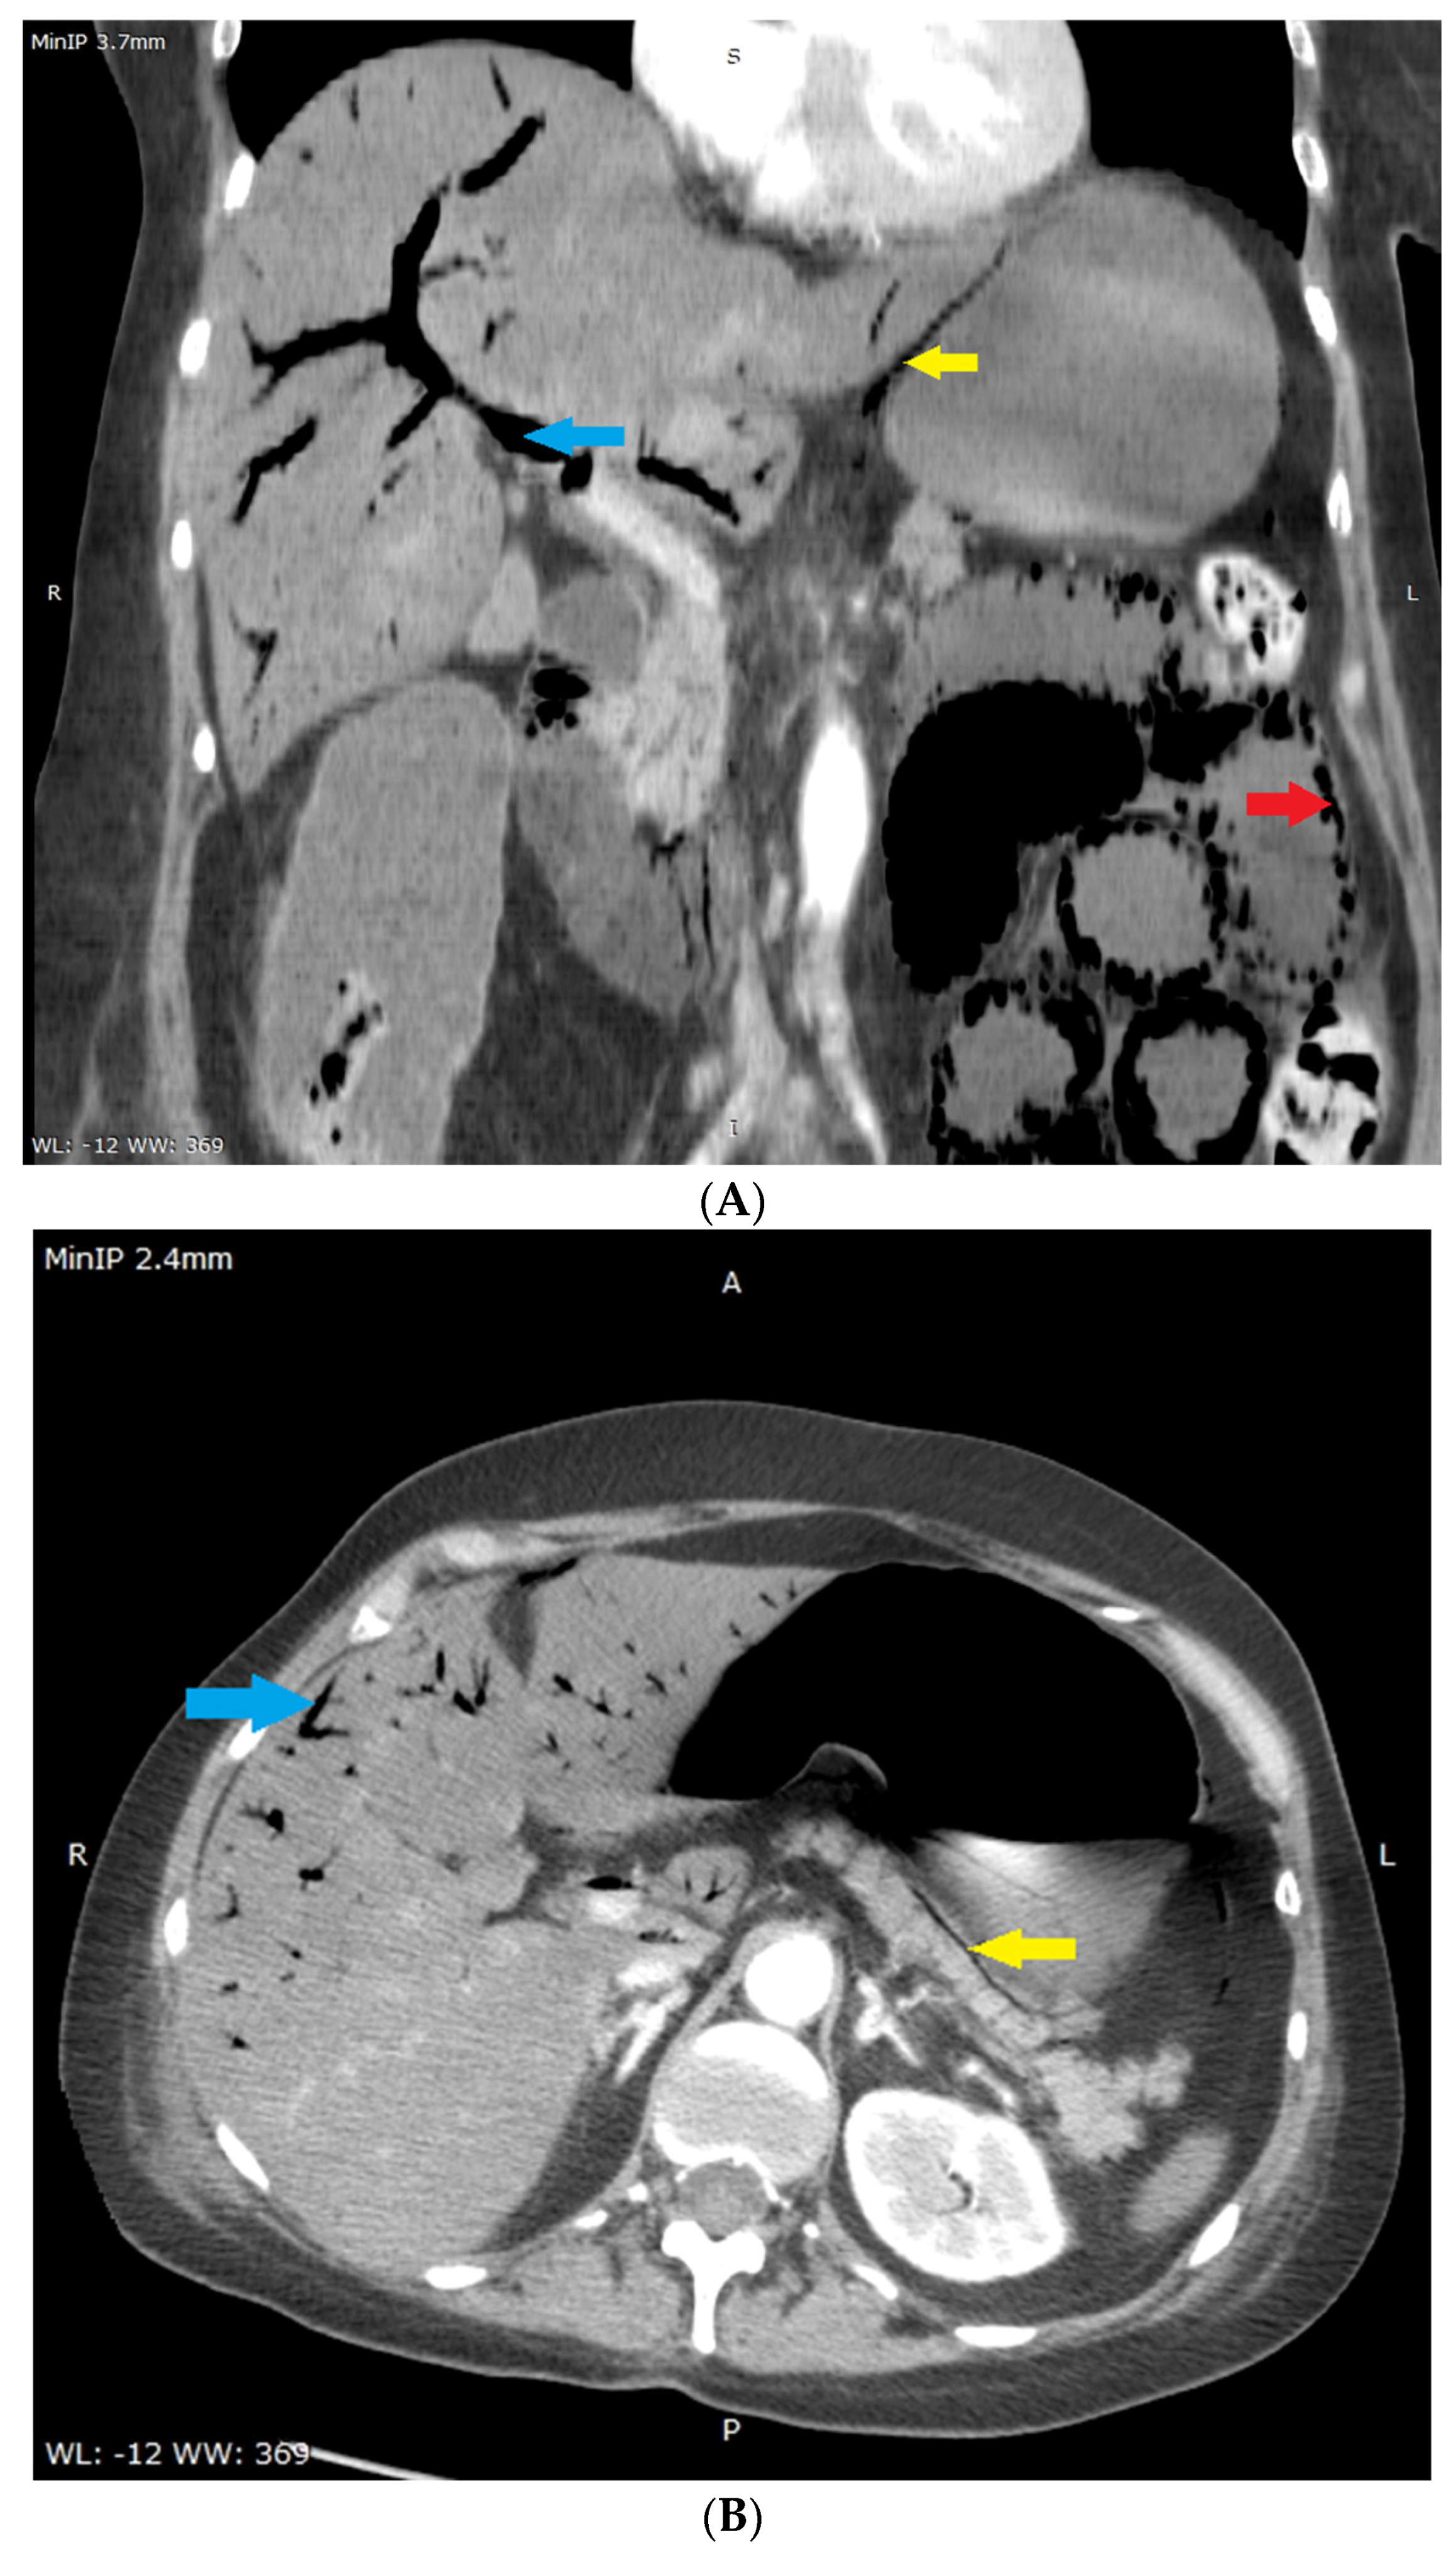

Sonographic Images of Hepatic Portal Venous Gas in a Patient with Gastrointestinal Ischemia